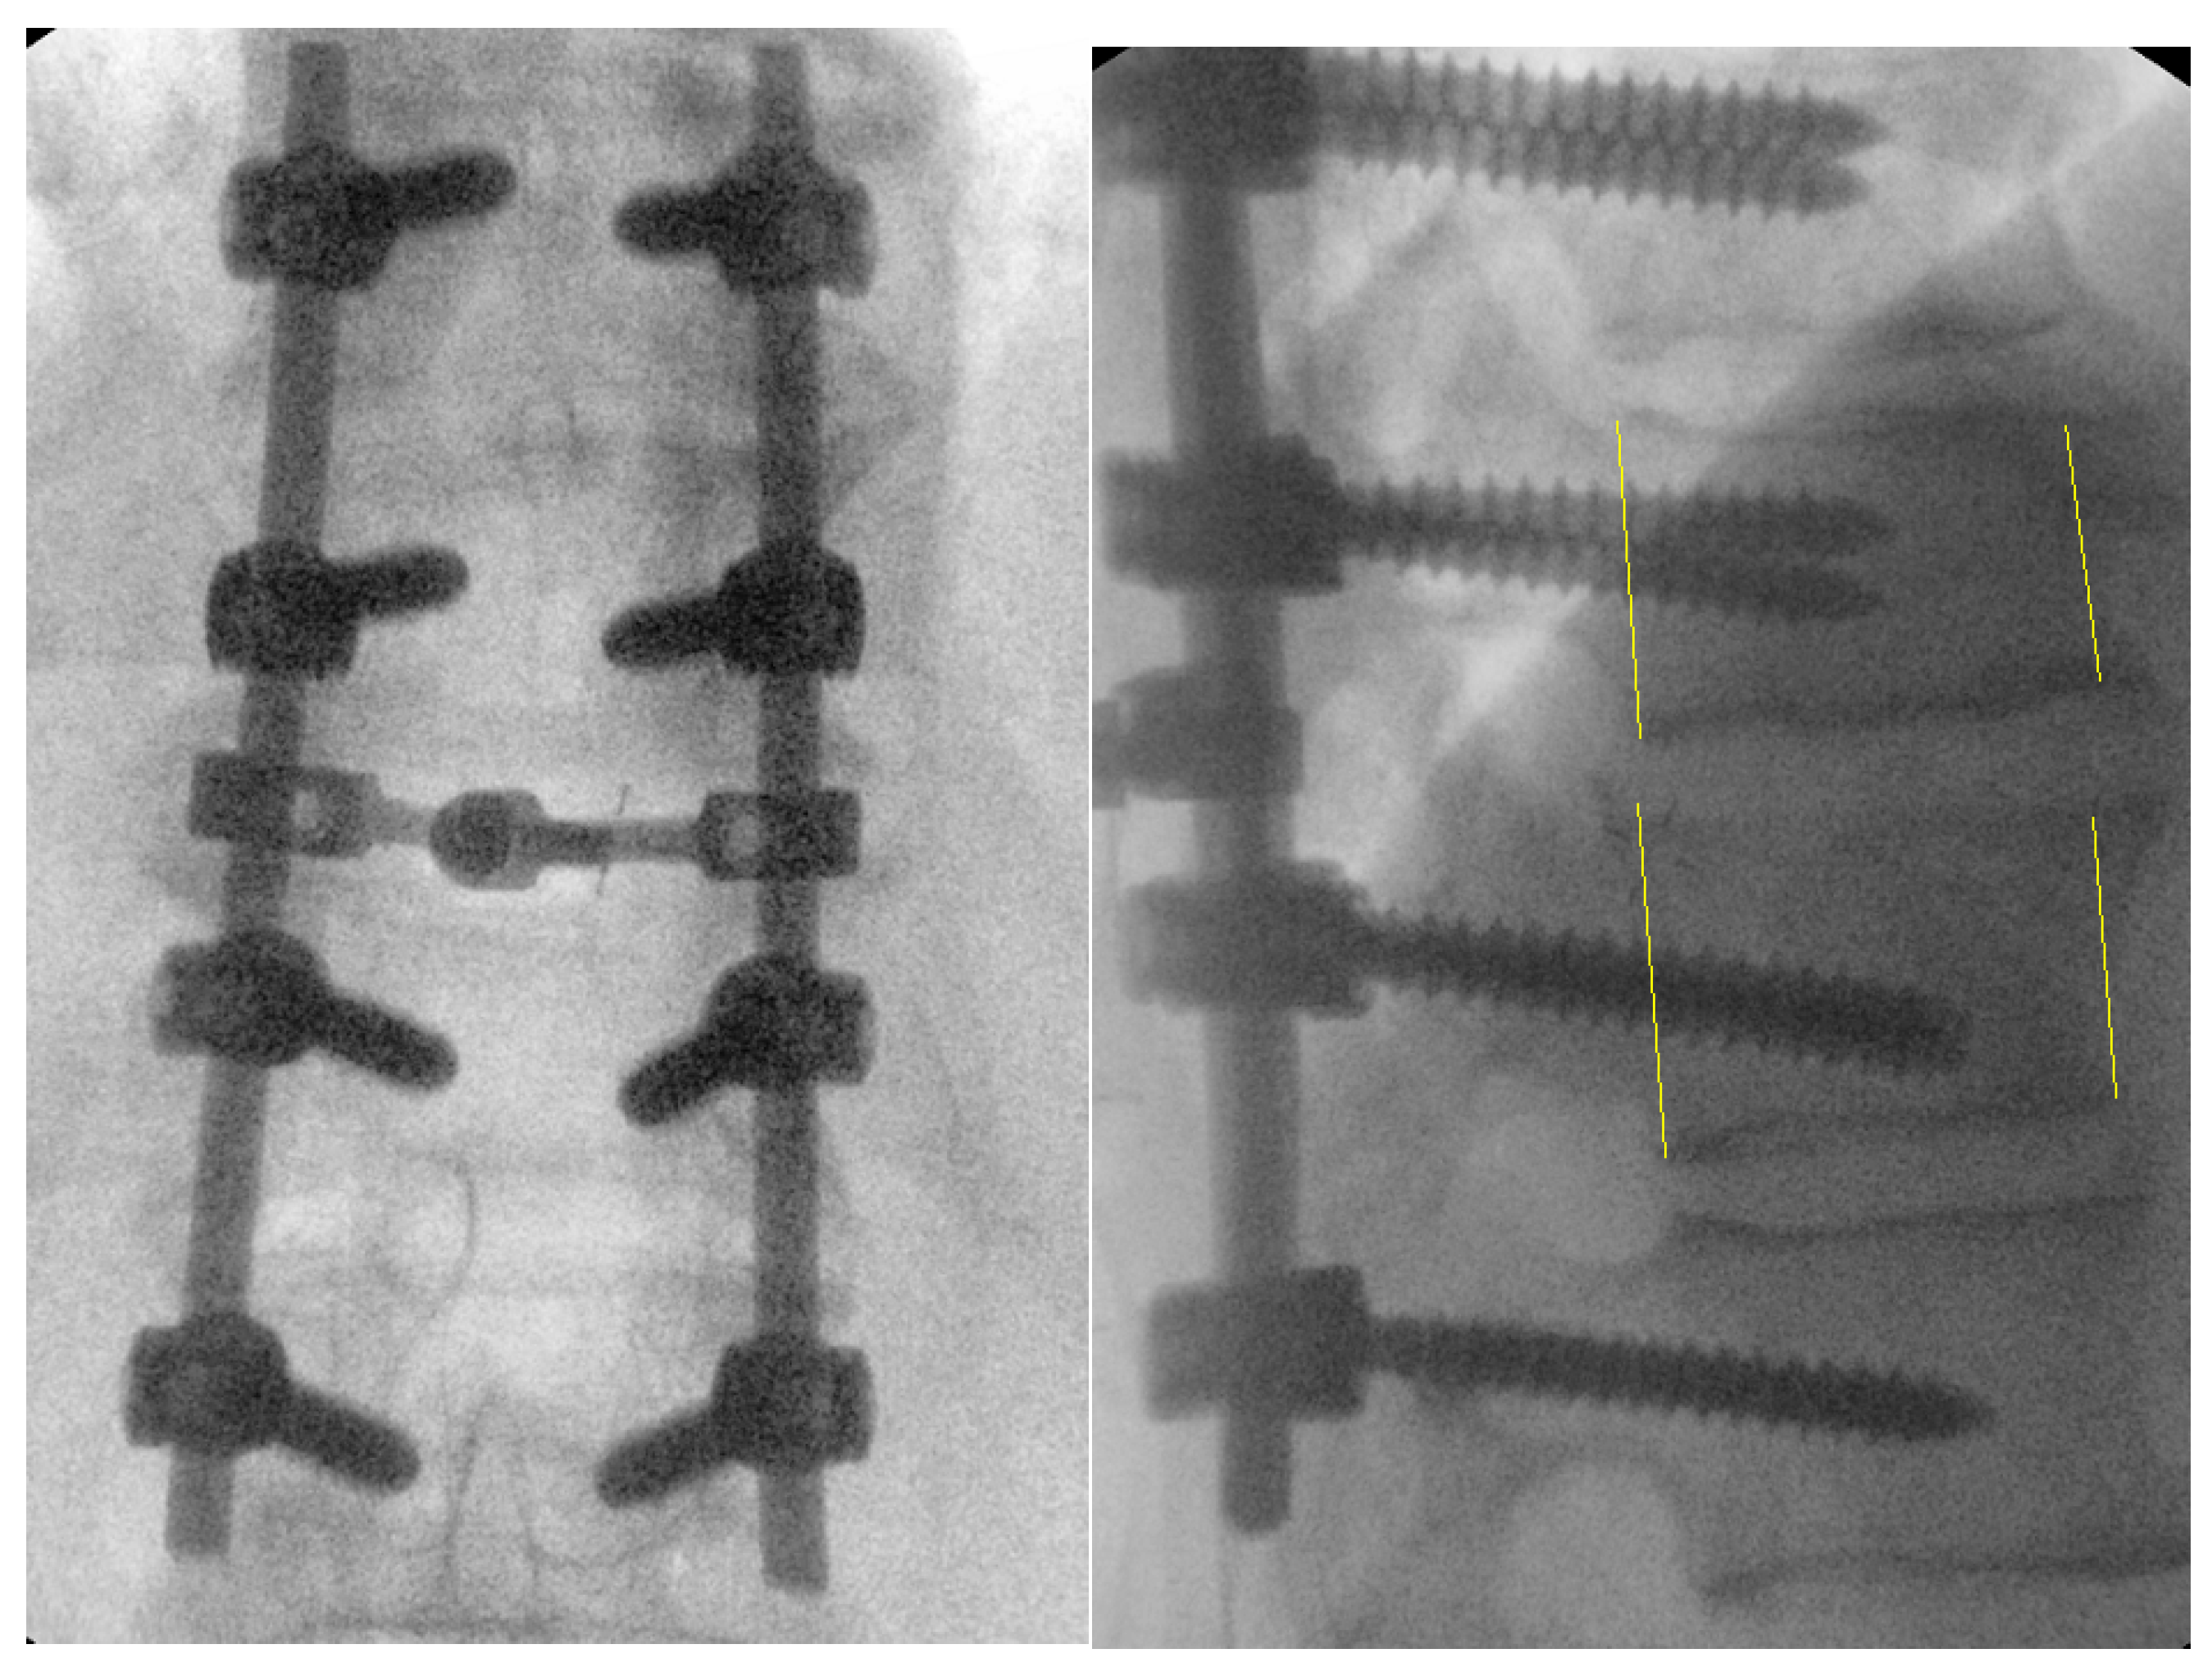

Figure 6.

Intraoperative fluoroscopic images after successful reduction, decompression, and posterolateral fusion of Th10-L1. Yellow lines represent the vertebral body height and the translation that is restored with the surgical fixation.

Figure 7.

Computerized tomography scan of thoracic fracture–dislocation (Th9/Th10) successfully and safely reduced using the described technique.